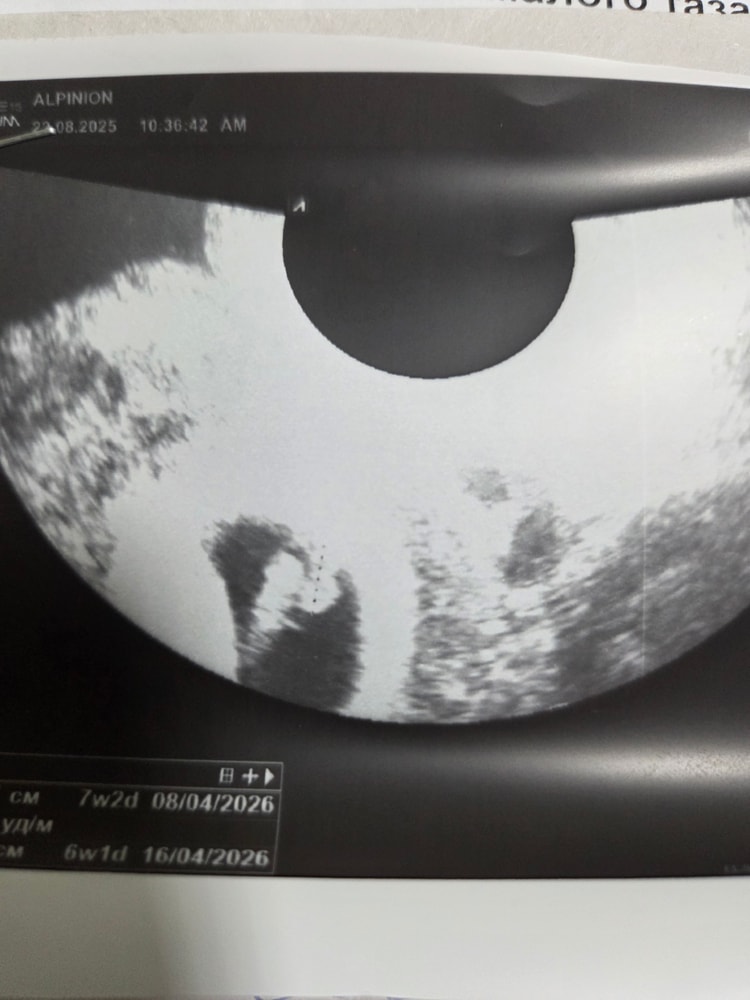

Вера , а это фото через 3 дня (на другом аппарате, более худшем). Здесь акушерских 6,0 недель. Изображение